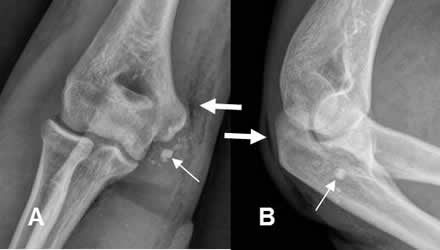

Fig 51. Avulsión del codo.

Desplazamiento inferior del núcleo de crecimiento, del epicóndilo medial.